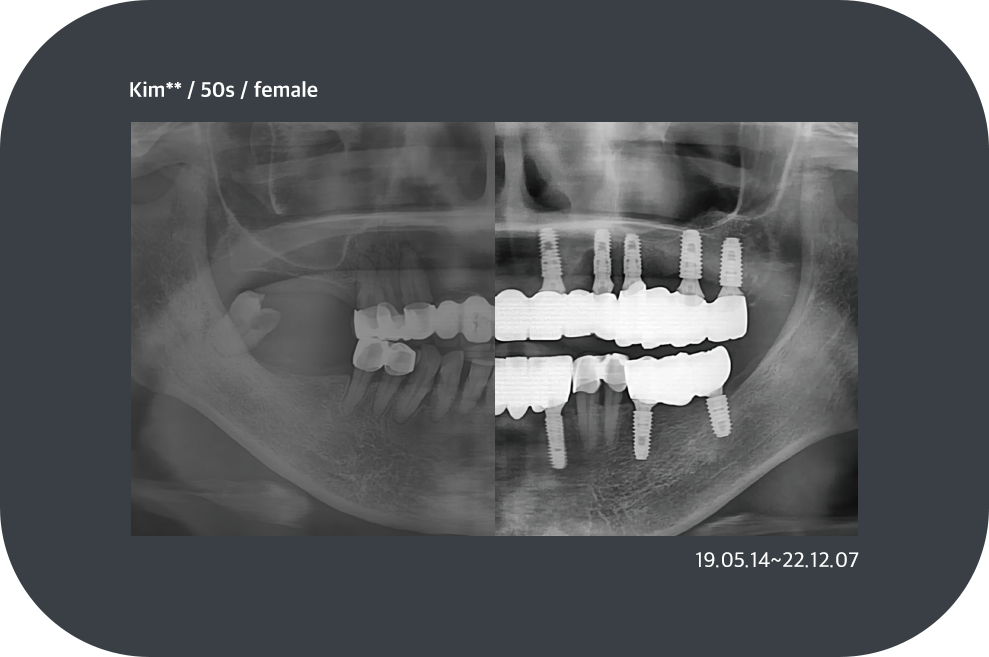

치료사례

임플란트 치료사례

*모든 증례 사진은 의료법 제23조, 제56조에 의거하여, 당사자의 동의하에 게시하였습니다.

*치료 사진은 모두 본원에서 치료한 환자분의 사진입니다.

*치료 사진은 모두 동일인의 사진이며, 동일조건에서 촬영하였습니다.

*개인의 차이에 따라 시술 및 수술 후 부작용이 발생할 수 있으며, 의료진과 충분한 상담을 받으시기 바랍니다.